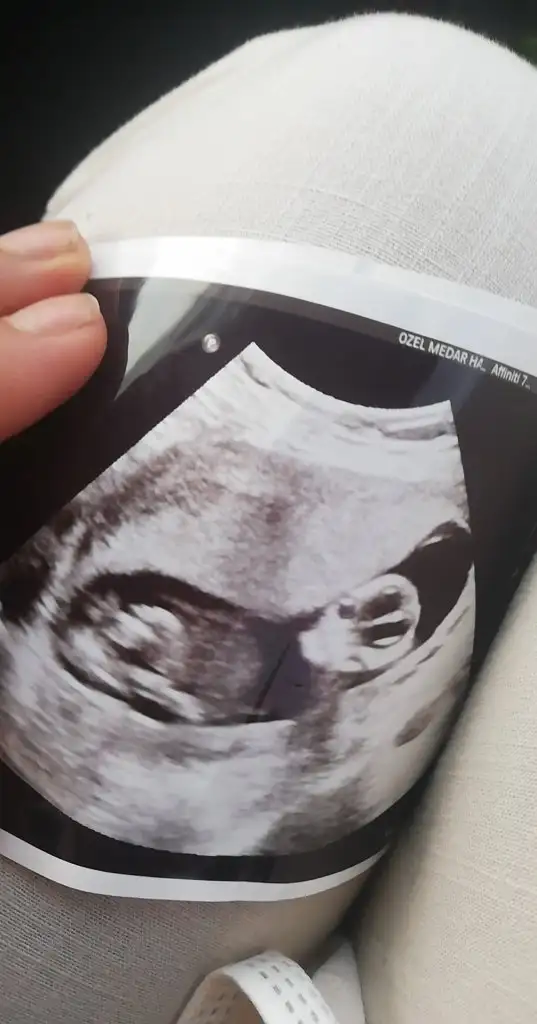

Merhaba lütfen tahmin yaparmısınız 2 yıl öncede yapmıştınız tutmuştu :)))

• 20210502_063853.webp

20210502_063853.webp

13,6 KB · Görüntüleme: 62